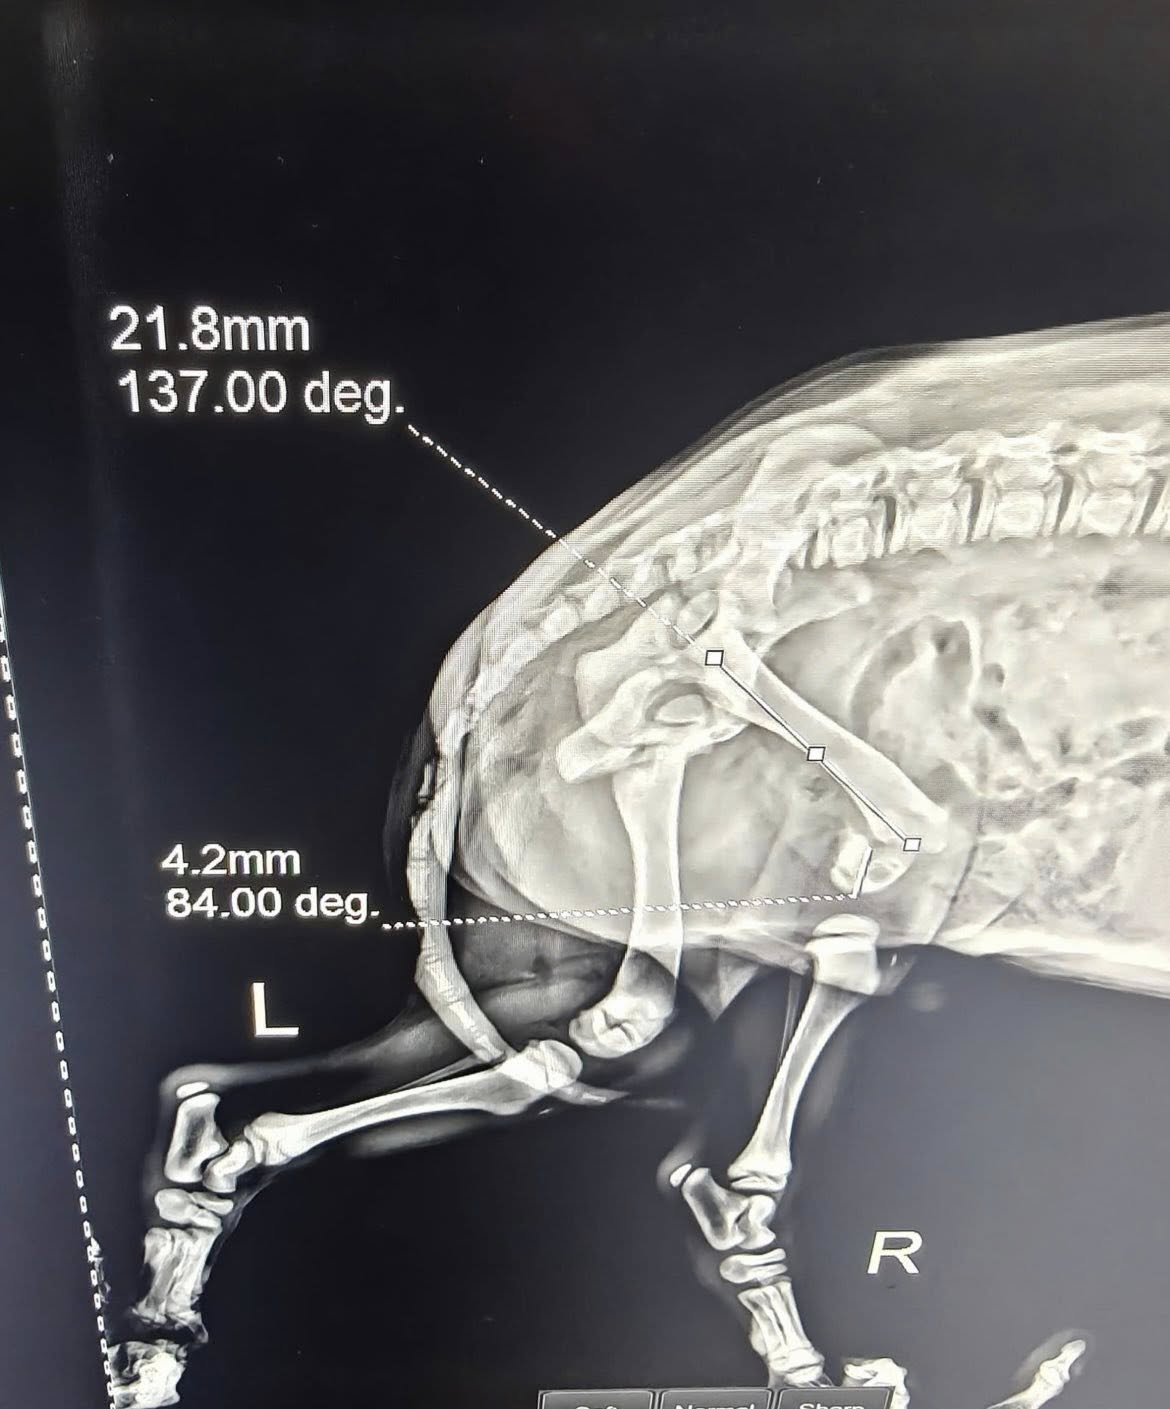

NaLa’s back leg was twisted at an unnatural angle, bleeding heavily. X-rays at the clinic later confirmed our worst fears: multiple broken bones. She was in shock, whimpering softly, her eyes wide with pain and fear. Whoever hit her didn’t stop. They just drove away, leaving her to suffer alone in the dark.

We rushed her to the emergency veterinary hospital. The doctors immediately began stabilizing her with IV fluids and strong pain relief. Her leg was swollen, fractured in several places, and would require surgery to repair. Without urgent care, infection and blood loss could have taken her life.

NaLa is now under round-the-clock medical supervision. She has already undergone her first procedures, but her road to recovery is long. She will need surgery, weeks of rehabilitation, and careful monitoring to learn how to walk again.